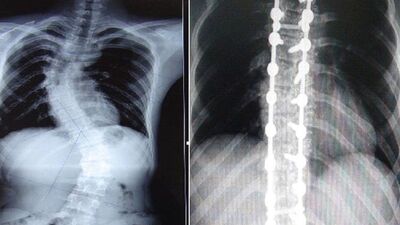

Fizik Tedavi ve Rehabilitasyon Uzmanı Prof. Dr. Cengiz Bahadır, Skolyoz'un diğer adıyla omurga eğriliğinin omurganın sağa veya sola eğilmesi olduğunu belirterek, "Skolyozda omurga sağa veya sola doğru eğimlenirken aynı anda bir dönme de meydana gelir. Normal bir omurgaya arkadan bakıldığında düz bir görüntüye sahiptir fakat skolyoz olan omurgada bir ya da birkaç tarafa eğim vardır. Aynı zamanda skolyoz olan bir omurgaya yandan bakıldığında da sırtta kamburlaşma görülür" dedi.

Skolyoz belirtilerini; "Başın bir tarafa doğru eğimli olması, Göğüs kafesinde asimetri, Kürek kemiklerinden birinin diğerine göre daha tümsek şeklinde olması, Kalçalar ve omuz seviyeleri eşit olmaması, Kollar ile vücut arasındaki mesafenin eşit olup olmaması ve Bacak eşitliklerinin aynı olmadığından şikayet edilmesi olarak sıralayan Prof. Dr. Cengiz Bahadır, "Skolyozun tanısı için dikkatli bir muayene ve basit bir röntgen filmi yeterlidir. Yalnız her eğrilik skolyoz değildir. Skolyozda vertebra eğimi 10 derecenin üzerinde olmalıdır. Bunun altındaki eğrilikler skolyoz olarak sınıflandırılmaz.